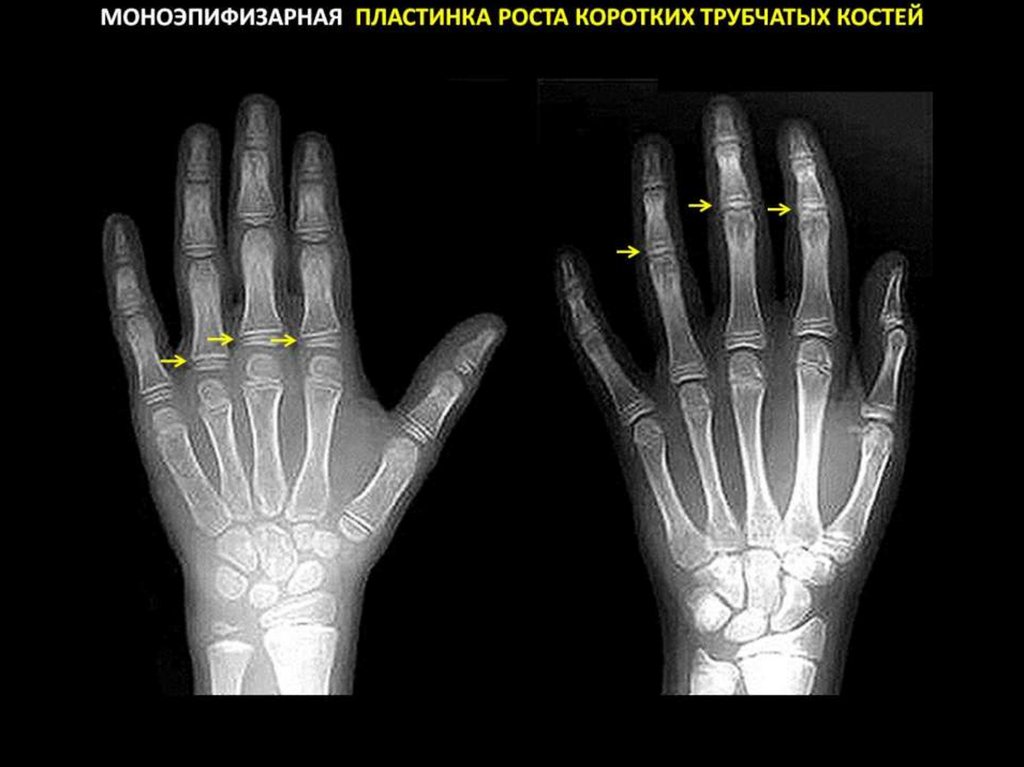

Функциональная анатомия и морфогенез костной ткани.

Компактная и губчатая кости. Адаптационный морфогенез костной ткани. Костная

система. Костная ткань. Виды костей. Кость как орган. Остеон. Механизмы

ремоделирования костной ткани и кости.